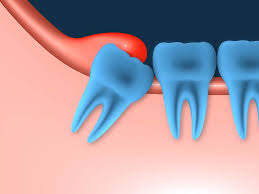

Eine Entzündung des Weisheitszahns ist sehr schmerzhaft und äußert sich daneben häufig mit Rötung Schwellung und Eiterbildung. In den ersten Monaten hatte ich ein Taubheitsgefühl in der Unterlippe das nach längerer Zeit verschwand. Der Weisheitszahn links unten entfernt der letzte endlich.

Häufig verläuft ein Nerv entweder durch die Wurzeln oder am Zahn entlang. Und bei nicht wenigen war es der fall dass der eingriff nah am nerv vorgenommen wurde das risiko also da war. Bevor ich meinen körper über jahre mit schmerzmitteln schädige und schmerzen leide würde ich mich diesem eingriff unterziehen.

Sie liegen sehr nah am Nerv weshalb der Arzt nur zwei auf Einmal zieht. Bei der lokalen Narkose besteht das Risiko vor allem dadurch dass durch die Nadel ein Nerv beschädigt wird.